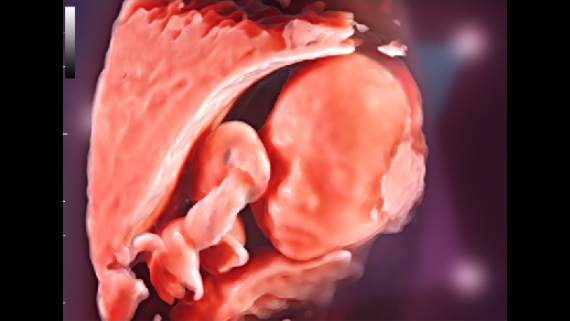

ImĂĄgenes clĂnicas